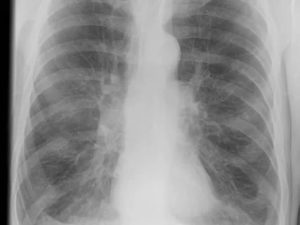

При сравнении флюорографии здоровых легких и принадлежащих курильщику в структуре последних легко определяются патологические отклонения.

Как уже упоминалось, при длительном и активном курении в органах дыхания происходят изменения. Рассмотрим подробнее отличие флюорографического снимка курильщика со стажем и здорового человека:

- Наличие уплотнений. В норме на снимке не должно быть очагов темного цвета в легких. При курении снижается эластичность тканей на определенных участках. Эти зоны уплотнения выглядят как затемнения.

- Объем сердца. У здорового человека размеры этого органа остаются в пределах нормы. При курении резко нарушается дыхательная функция. Это приводит к расширению отделов сердца. Орган выглядит на снимке несколько увеличенным.

- Сосудистый рисунок. У курильщиков на снимке более резко выражена сеть сосудов, чем у здоровых людей. Это связано с тем, что воздействие никотина и продуктов горения приводит к образованию наростов на артериях и венах.

- Пятна на легких. Табачные смолы закупоривают поры легких. Образуются участки со сниженным газообменом, которые выглядят на снимке как темные или светлые включения. В норме на снимке не должно определяться пятен.

- Легочный рисунок. У курильщиков тени от сосудов на снимке выражены нечетко. В этом случае врачи говорят об ослаблении легочного рисунка. Такой признак указывает на начало фиброзных изменений в тканях.

- Утолщение стенок бронхов. Это является следствием постоянного раздражения дыхательных путей смолами и никотином. Такая особенность указывает на наличие хронического бронхита.

Однако даже по таким признакам нельзя сделать однозначный вывод о том, что пациент курит. Ведь подобные изменения встречаются и у людей без вредных привычек. Чтобы установить точную этиологию отклонений, врачи назначают дополнительные обследования.